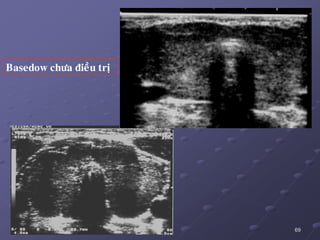

Basedow chöa ñieàu trò

1.1/. Basedow:

 SA coù 2 kieåu hình aûnh:

_ Taêng saûn lan toaû ñoàng nhaát vôùi vaøi vuøng maïch maùu daõn .

_ 86 % TG khoâng ñoàng nhaát khoâng toå chöùc hoaù, echo keùm

gioáng nhö vieâm gíap hay hình aûnh nhaân giaû.

 Ño ñaït theå tích tuyeán giaùp raát caàn thieát sau phaãu thuaät caét giaùp

(taùi phaùt 20%), khi coù chæ ñònh ÑT baèng ioát phoùng xaï.

 Suy giaùp sau phaãu thuaät 1%, sau ÑT ioát phoùng xaï25%.

 Keát hôïp vôùi K chieám 0,3 – 16,6%, daïng nhuù >> daïng nang.